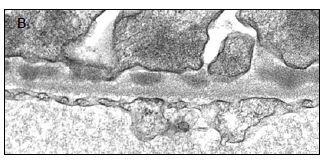

图2.电镜显示沉积物聚集于上皮下间隙